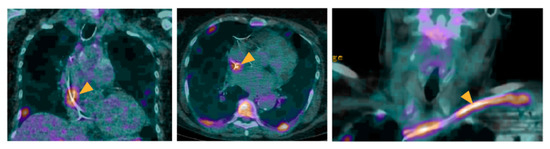

- Mikail, N.; Benali, K.; Ou, P.; Slama, J.; Hyafil, F.; Le Guludec, D.; Rouzet, F. Detection of Mycotic Aneurysms of Lower Limbs by Whole-Body (18)F-FDG-PET. JACC Cardiovasc. Imaging 2015, 8, 859–862. [Google Scholar] [CrossRef]

- Amraoui, S.; Tlili, G.; Sohal, M.; Berte, B.; Hindié, E.; Ritter, P.; Ploux, S.; Denis, A.; Derval, N.; Rinaldi, C.A.; et al. Contribution of PET Imaging to the Diagnosis of Septic Embolism in Patients With Pacing Lead Endocarditis. JACC Cardiovasc. Imaging 2016, 9, 283–290. [Google Scholar] [CrossRef] [PubMed]